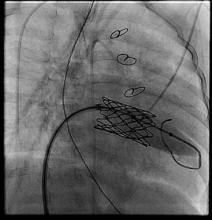

Three patients underwent sequential expansion about 6 months after implantation. After valve expansion, the median balloon size was 12 mm, ranging from 12 to 16 mm. None of the patients developed worsening valvular function and all had relief of obstruction. Transcatheter intervention was used to correct a paravalvular leak in one patient and to treat a left ventricular outflow tract problem in another. None of the patients developed endocarditis or a strut fracture, "although I worry about strut fracture if aggressive stent resection and manipulation is performed," he said at the meeting, which was sponsored by the AATS.

Dr. Emani offered some procedural tips. First, the Melody valve must be optimized for surgical implantation in infants. The length of the valve must be reduced by trimming it to reduce the chance of LVOTO or pulmonary vein obstruction. He recommends sizing the valves by echocardiogram and fixating the distal stent to the inferior free wall of the ventricle.